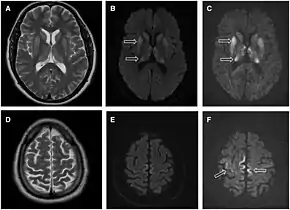

Imaging of the brain may be performed during medical evaluation, both to rule out other causes and to obtain supportive evidence for diagnosis. Imaging findings are variable in their appearance, and also variable in sensitivity and specificity.[43] While imaging plays a lesser role in diagnosis of CJD,[44] characteristic findings on brain MRI in some cases may precede onset of clinical manifestations.[45]

Brain MRI is the most useful imaging modality for changes related to CJD. Of the MRI sequences, diffuse-weighted imaging sequences are most sensitive.[46] Characteristic findings are as follows:

- Focal or diffuse diffusion-restriction involving the cerebral cortex and/or basal ganglia. In about 24% of cases DWI shows only cortical hyperintensity; in 68%, cortical and subcortical abnormalities; and in 5%, only subcortical anomalies.[47] The most iconic and striking cortical abnormality has been called "cortical ribboning" or "cortical ribbon sign" due to hyperintensities resembling ribbons appearing in the cortex on MRI.[48] The involvement of the thalamus can be found in sCJD, is even stronger and constant in vCJD.[49]

- Varying degree of symmetric T2 hyperintense signal changes in the basal ganglia (i.e., caudate and putamen), and to a lesser extent globus pallidus and occipital cortex.[44]

- Cerebellar atrophy

Brain FDG PET-CT tends to be markedly abnormal, and is increasingly used in the investigation of dementias.

- Patients with CJD will normally have hypometabolism on FDG PET.[50]